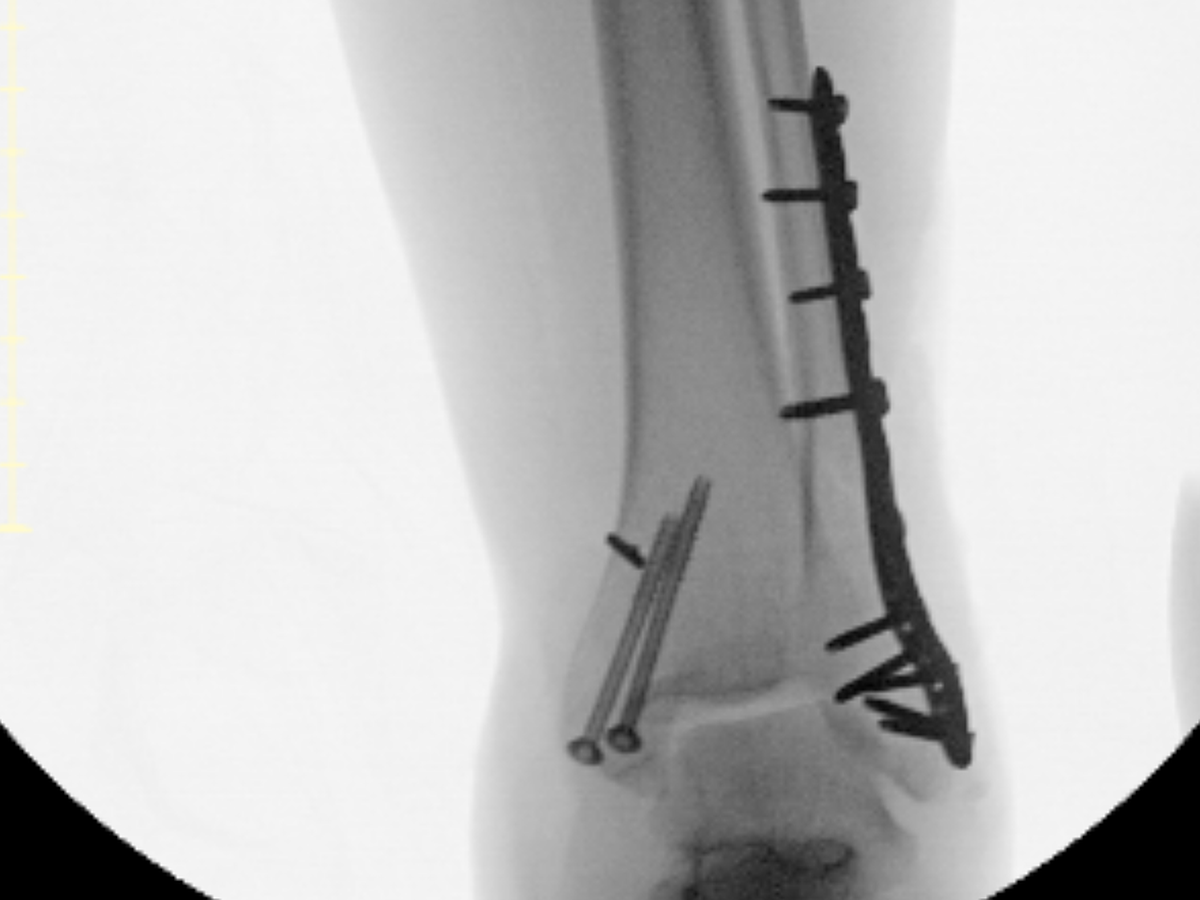

As most of you know, I have worked as a nurse for the last nearly 7 years. I love my work as a nurse, and when I got injured at the end of January, I was devastated that my travel nursing agency had to cancel my contract. I injured my ankle on 1/24/25 when I had a nasty fall. I broke my ankle in 3 places and separated the joint. I am currently unable to work as a nurse and am finding out firsthand how hard it is to navigate life when you can't work in your chosen field. I had surgery about 2 weeks ago, and I am looking at 12 weeks of recovery time for my injury. I am seeking work from home employment and attempting to get benefits for those who are unemployed in the mean time.